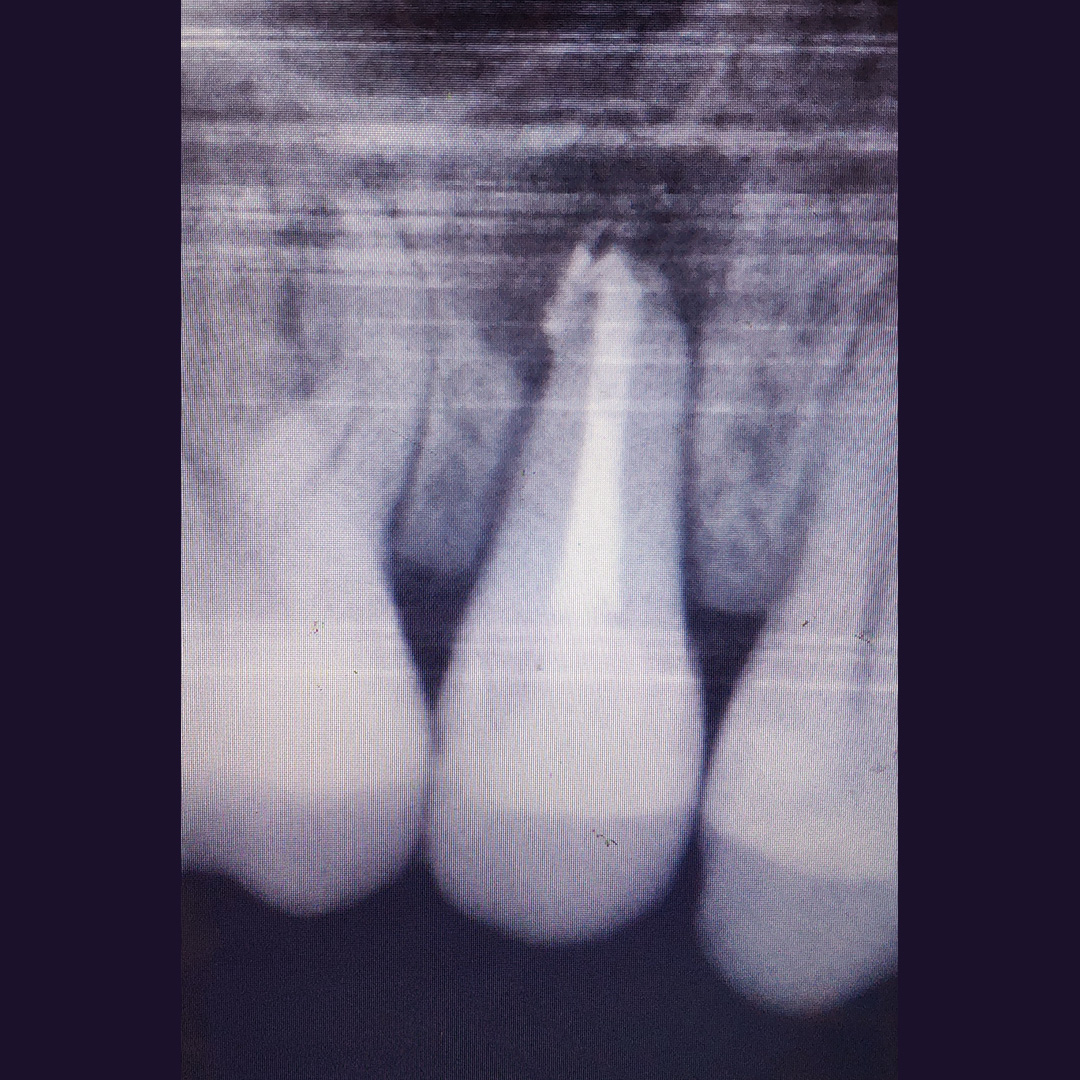

До и после лечения

В клинику обратился пациент с жалобами на постоянные ноющие боли и резкую боль при накусывании. С его слов, зуб ранее лечили в другом ЛПУ по поводу хронического фиброзного пульпита. После осмотра врач Черных Антон Алексеевич проанализировал рентгенограмму, поставил диагноз и провёл повторное эндодонтическое лечение зуба 1.5.

Перелечивание каналов необходимо при воспалении тканей, окружающих зуб. Требуется при попадании инфекции или при дефектах ранее проведённого лечения: недопломбированные участки, рассосавшийся пломбировочный материал внутри каналов.

В ходе лечения были проведены следующие работы:

- эндодонтическое лечение с применением коффердама

- постоянная пломбировка корневых каналов

- восстановление коронковой части зуба